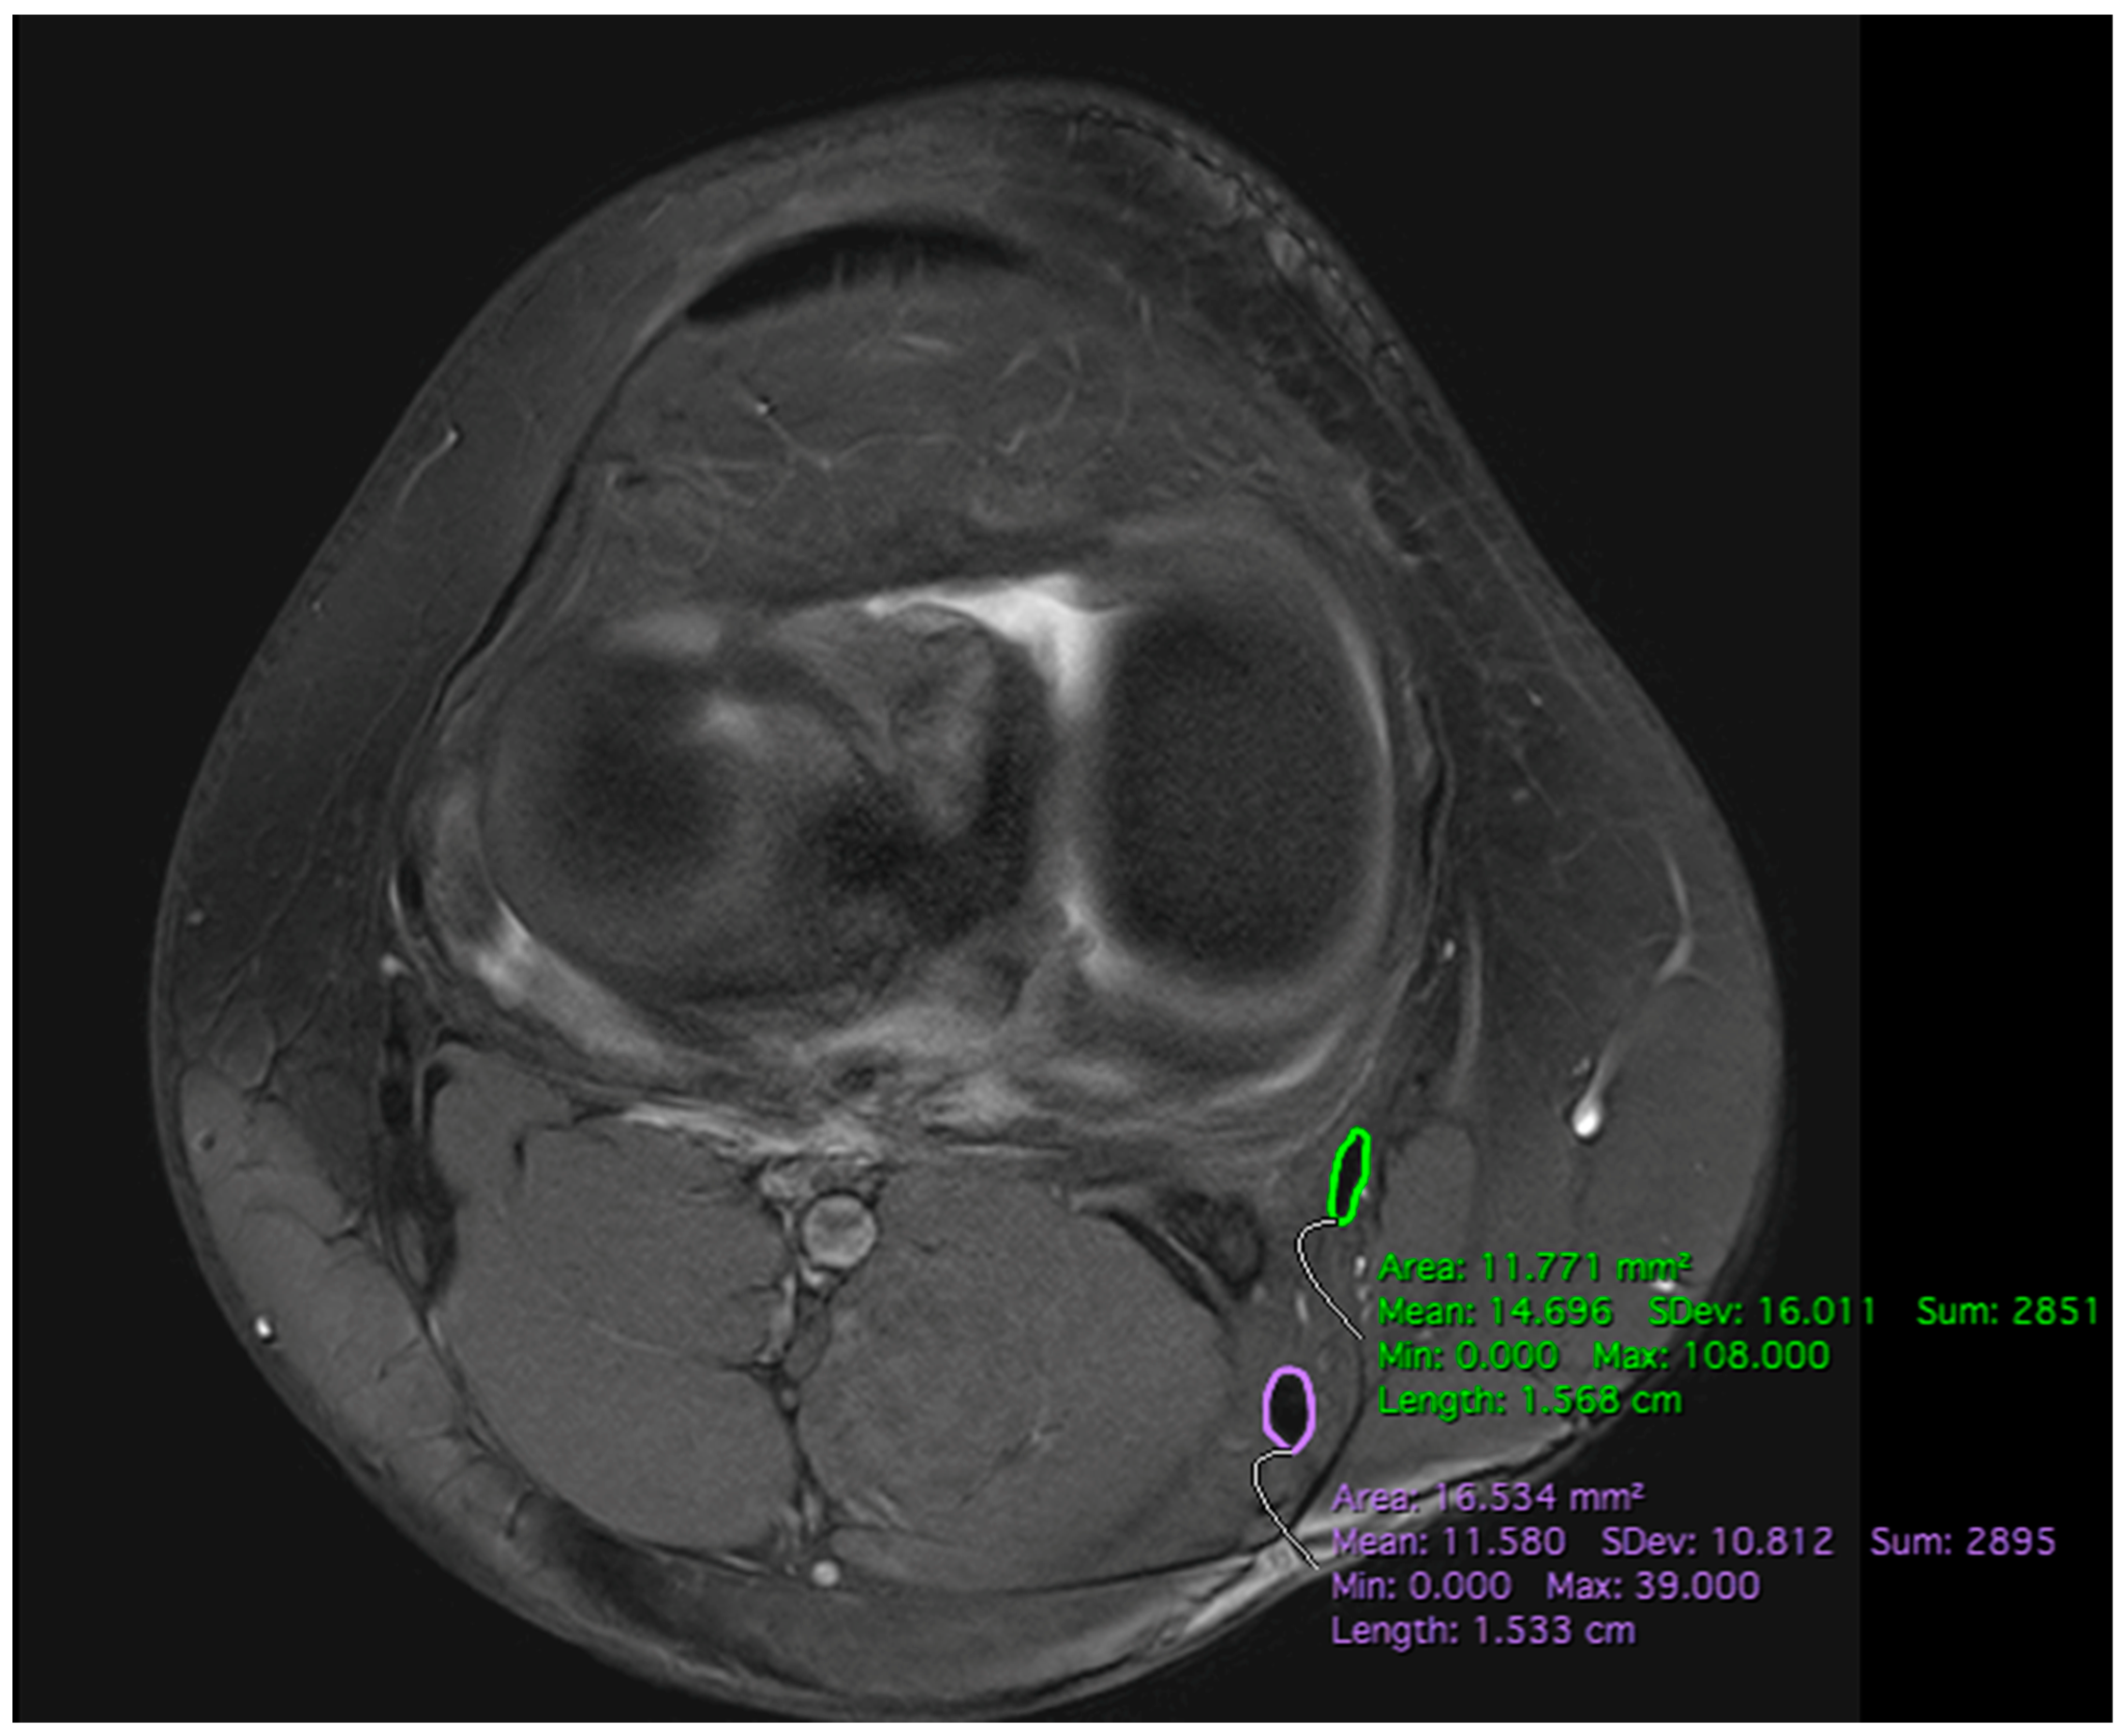

2.2. MRI Measurements

3.2. MRI CSA STGT